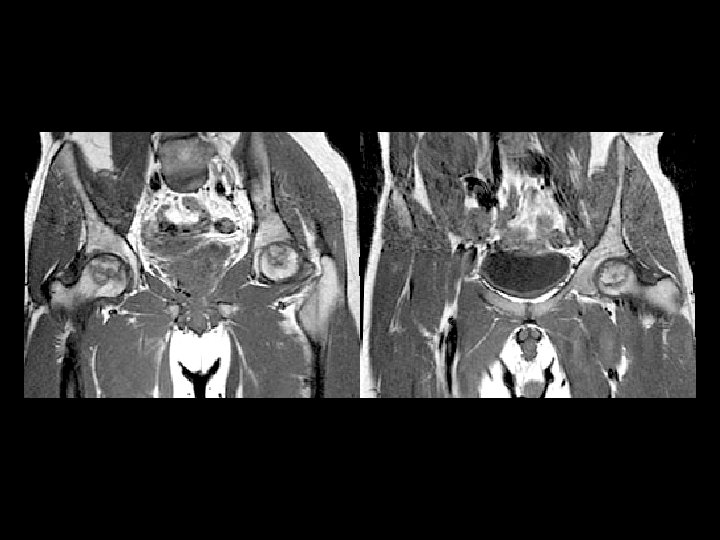

Femoral Head AVN • Findings: – bilateral femoral head AVN w/o collapse – right pelvic renal tx • Ddx: – Pancreatitis – Sickle Cell Dz – Caison’s Dz – etc…